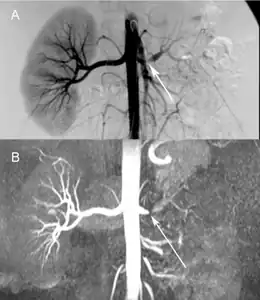

- Comparison a) Digital subtraction arteriography and b) Unenhanced Magnetic resonance angiography of suboclusive left renal artery stenosis arrows